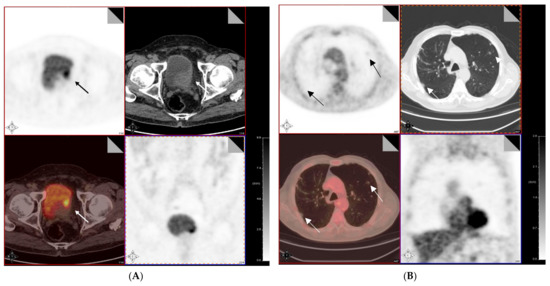

- Van de Putte, E.E.F.; Vegt, E.; Mertens, L.S.; Bruining, A.; Hendricksen, K.; van der Heijden, M.S.; Horenblas, S.; van Rhijn, B.W.G. FDG-PET/CT for response evaluation of invasive bladder cancer following neoadjuvant chemotherapy. Int. Urol. Nephrol. 2017, 49, 1585–1591. [Google Scholar] [CrossRef]

- Kollberg, P.; Almquist, H.; Bläckberg, M.; Cwikiel, M.; Gudjonsson, S.; Lyttkens, K.; Patschan, O.; Liedberg, F. [18F] Fluorodeoxyglucose-positron emission tomography/computed tomography response evaluation can predict histological response at surgery after induction chemotherapy for oligometastatic bladder cancer. Scand. J. Urol. 2017, 51, 308–313. [Google Scholar] [CrossRef]

- Alongi, P.; Caobelli, F.; Gentile, R.; Stefano, A.; Russo, G.; Albano, D.; Baldari, S.; Gilardi, M.C.; Midiri, M. Recurrent bladder carcinoma: Clinical and prognostic role of 18 F-FDG PET/CT. Eur. J. Nucl. Med. Mol. Imaging 2016, 44, 224–233. [Google Scholar] [CrossRef]